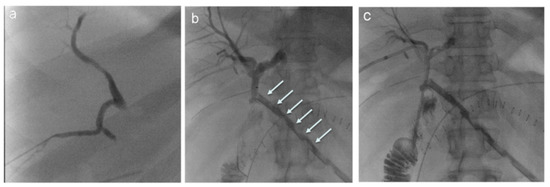

- Henry, A.C.; Smits, F.J.; van Lienden, K.; van den Heuvel, D.A.F.; Hofman, L.; Busch, O.R.; van Delden, O.M.; Zijlstra, I.A.; Schreuder, S.M.; Lamers, A.B.; et al. Biliopancreatic and biliary leak after pancreatoduodenectomy treated by percutaneous transhepatic biliary drainage. HPB 2022, 24, 489–497. [Google Scholar] [CrossRef]

- Pedicini, V.; Poretti, D.; Mauri, G.; Trimboli, M.; Brambilla, G.; Sconfienza, L.M.; Cornalba, G.; Sardanelli, F. Management of post-surgical biliary leakage with percutaneous transhepatic biliary drainage (PTBD) and occlusion balloon (OB) in patients without dilatation of the biliary tree: Preliminary results. Eur. Radiol. 2010, 20, 1061–1068. [Google Scholar] [CrossRef]

- Mansueto, G.; Gatti, F.L.; Boninsegna, E.; Conci, S.; Guglielmi, A.; Contro, A. Biliary leakage after hepatobiliary and pancreatic surgery: A classification system to guide the proper percutaneous treatment. Cardiovasc. Interv. Radiol. 2020, 43, 302–310. [Google Scholar] [CrossRef]